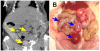

Methods: We established a murine model of metastatic EOC by intraperitoneal injection of A2780/CP70 human ovarian cancer cells into nude mice. We developed a murine hyperthermic intraperitoneal chemotherapy model to treat the mice. Mice with peritoneal metastasis were perfused for 1 h with 3 mg/kg cisplatin ± 26 mg/kg NaAsO2 at 37 or 43°C. Tumors and tissues were collected at 0 and 24 h after treatment.